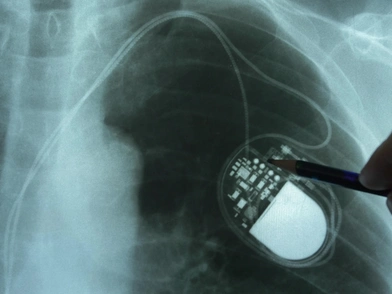

Ο βηματοδότης είναι μία συσκευή που έχει σώσει αμέτρητους καρδιοπαθείς παγκοσμίως. Είναι ένα ασύρματο μηχάνημα που εμφυτεύεται στο εσωτερικό του άνω μέρους του στήθους κάτω από την κλείδα, και λειτουργεί στέλνοντας έναν μικρό ηλεκτρικό παλμό κάθε φορά που ανιχνεύει κάτι παράταιρο στον χτύπο της καρδιάς.

Ο βηματοδότης αποτελείται από ένα σύνθετο ηλεκτρονικό κύκλωμα, που παρακολουθεί, αναλύει και καταγράφει κάθε καρδιακό χτύπο και εάν χρειαστεί, απελευθερώνει ανεπαίσθητα ερεθίσματα χαμηλής έντασης τα οποία ρυθμίζουν τη δραστηριότητα της καρδιάς.